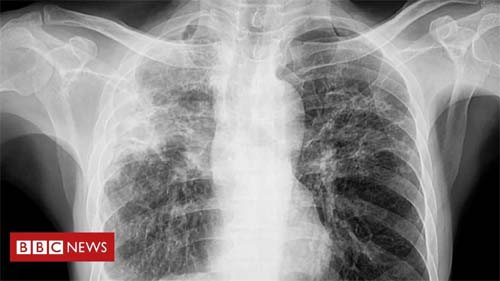

CRÉDITO,GETTY IMAGES

Tosse que persiste por mais de três semanas é o principal sintoma da tuberculose pulmonar